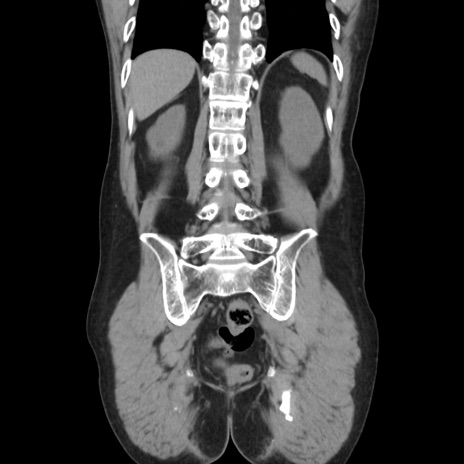

症例37(冠状断像)

【症例】40歳代 男性

【主訴】腹痛

【現病歴】4時間ほど前に電車に乗車中に臍部上より腹痛出現。徐々に増悪し起立困難となり、救急外来受診。生ものは数日食べていない。今朝お雑煮を食べた。

【身体所見】BT 36.8℃、BP 117/84mmHg、HR 91/min、SpO2 97%、苦悶様、腹部:臍上部広範囲圧痛あり、反跳痛±

【データ】WBC 8100、CRP 0.03